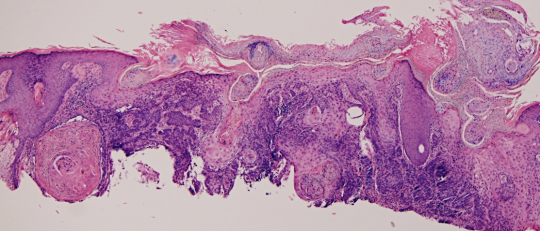

VA15: Right Dorsal Hand, Squamous Cell Carcinoma, Invasive, Keratoacanthoma type

- Arrows indicate extent of squamous mass